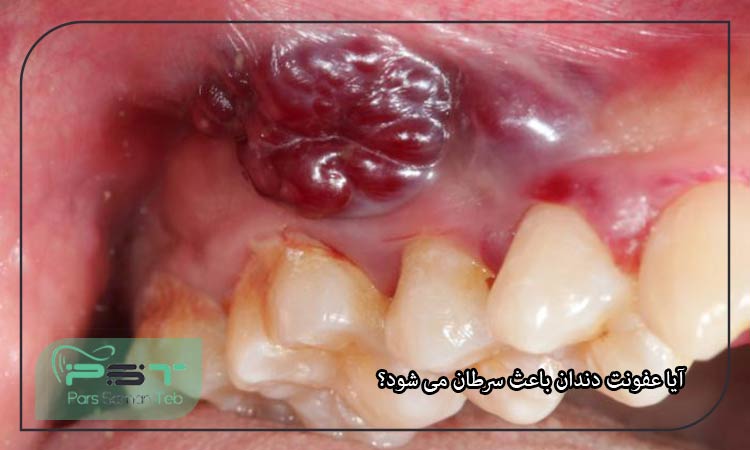

به تودههای غیرطبیعی در دهان اشاره دارد که میتوانند خوشخیم یا بدخیم باشند. بارز ترین علائم این بیماری های خطرناک، شامل وجود توده یا زخم در دهان و تغییر در رنگ یا شکل لثهها می شود. درمان این بیماری بستگی به نوع و شدت تومور دارد و احتمالا شامل جراحی، شیمیدرمانی یا پرتو درمانی خواهد بود.

آیا عفونت دندان باعث سرطان می شود؟

عفونت دندان، بهویژه عفونتهای مزمن لثه (پریودنتیت)، باعث التهاب مزمن در بدن می شود. این التهاب به آسیب بافتهای اطراف و افزایش خطر ابتلا به بیماریهای جدیتر از جمله برخی انواع سرطان منجر خواهد شد. علاوه بر این، افرادی که دچار عفونت دندان و بیماریهای لثه هستند و در عین حال سیگار میکشند یا الکل مصرف میکنند، در معرض خطر بالاتری برای ابتلا به سرطانهای دهان و حلق قرار دارند. در عین حال، بیماریهای مزمنی مانند دیابت که با عفونت دندان مرتبط هستند، احتمال بروز التهاب و خطر ابتلا به سرطان را افزایش میدهد. در حالی که عفونت دندان بهتنهایی عامل ایجاد سرطان نیست، اما میتواند به طور غیرمستقیم با افزایش التهاب و مشکلات بهداشتی، خطر ابتلا به برخی نوعهای سرطان را افزایش دهد. به همین دلیل، حفظ بهداشت دهان و درمان بهموقع مشکلات دندانی اهمیت زیادی دارد. در صورت وجود نگرانی درباره سلامت دهان یا علائم غیرعادی، هرچه سریع تر به دندانپزشک یا پزشک متخصص مراجعه کنید.